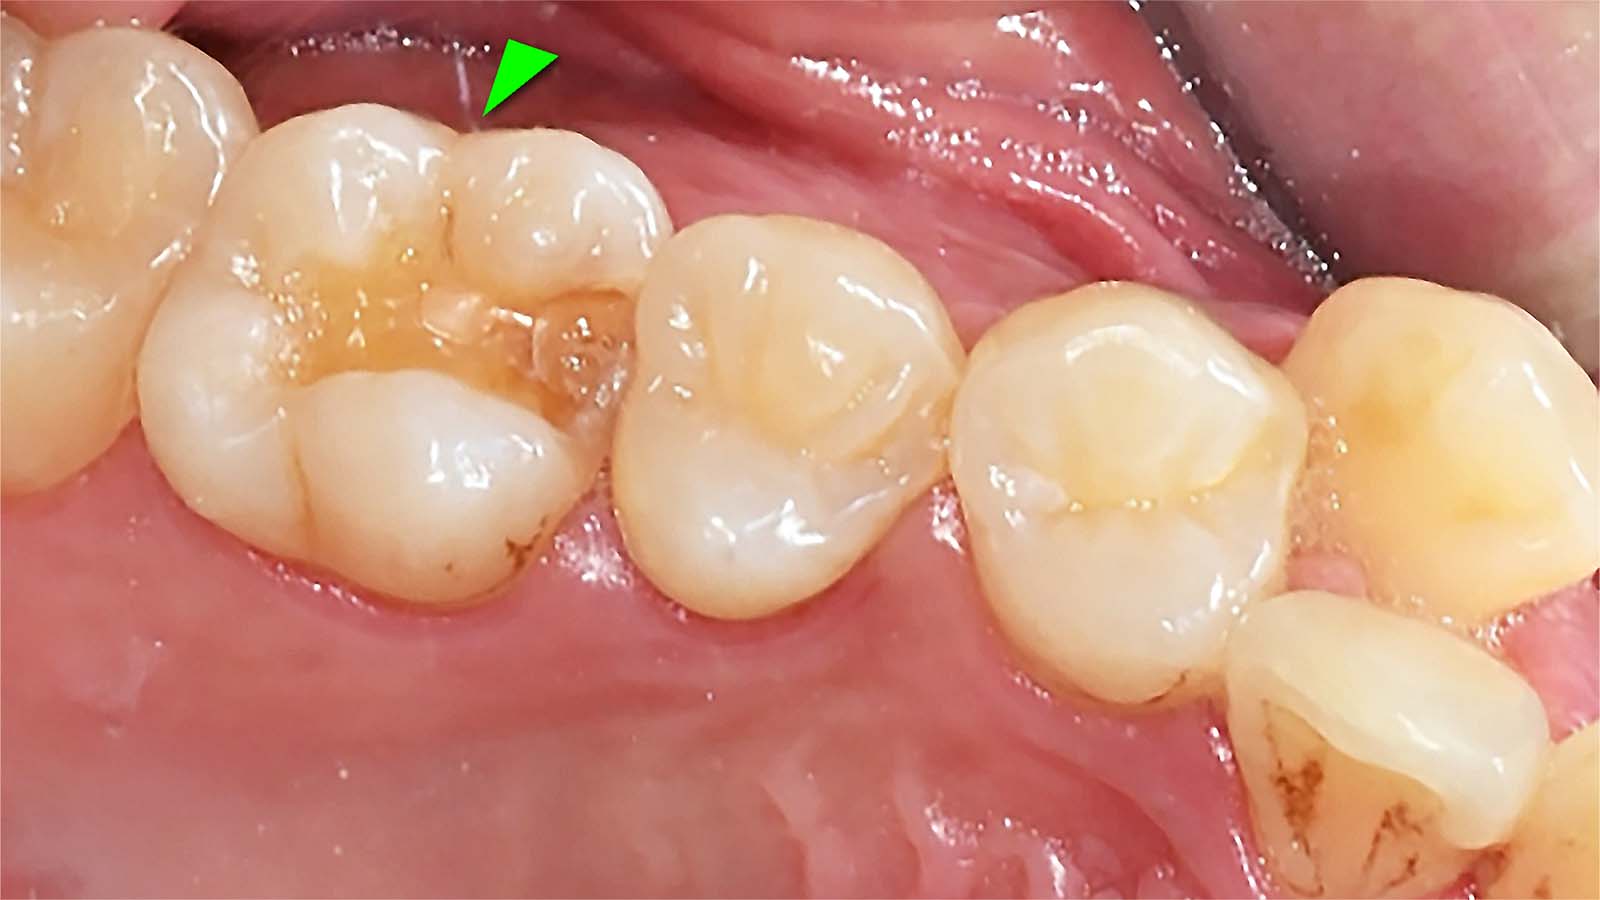

다음은 충치를 제거하고 표면을 깨끗하게 다듬은 모습입니다. 레진으로 떼우기에는 범위가 넓고 깊습니다.

충치를 제거하고 표면을 다듬은 모습

이제 약간의 손재주와 끈기가 필요합니다. 레진을 한 층 한 층 쌓아서 원래의 이상적인 치아의 모습을 만듭니다. 레진 빌드업은 치과의사의 손에서 시작하여 손에서 끝나는 치료입니다. 다음은 레진빌드업 치료결과입니다. 다른 치아와 구분이 안됩니다.

레진빌드업 치료 결과